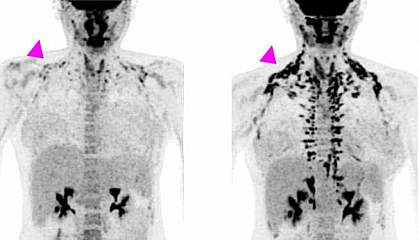

All of the women underwent positron emission tomography (PET)/CT scanning before treatment and at the end of the study, to measure brown fat activity. The researchers also measured the women's metabolism, cholesterol and other markers of heart health, and blood sugar and insulin sensitivity (the ability to use insulin properly and control blood sugar levels). Results appeared on January 21, 2020, in the Journal of Clinical Investigation.

After four weeks of treatment, the women’s metabolism at rest was almost 6% higher, although their weight or overall body composition—the ratio of fat to muscle—hadn’t changed. Brown fat activity, as measured by PET/CT, also increased during the study. The largest changes were found in women who had less brown fat activity to begin with.